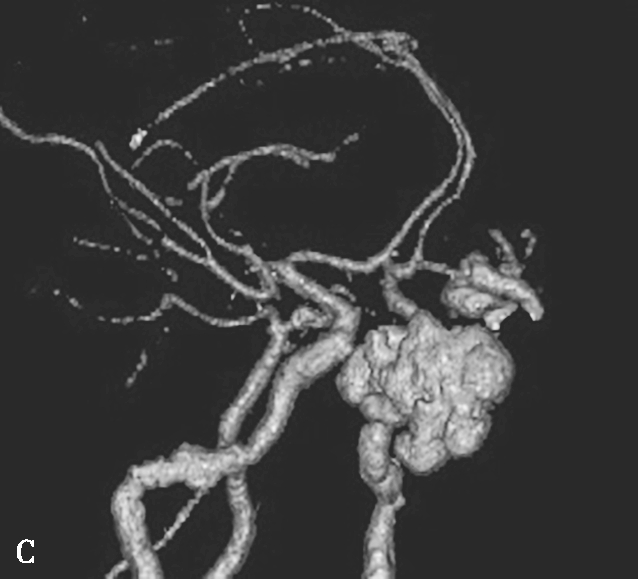

图1-2-6 左侧颈内动脉创伤后假性动脉瘤突入蝶窦

患者男,36岁,车祸伤后左侧额部硬膜外血肿清除并颅骨去骨瓣减压术后半年,间断大量鼻出血半个月就诊。A.颅脑CTA检查MPR横断面重组,可见蝶窦内软组织密度影,部分与颈内动脉同步均匀强化,并通过蝶窦骨质缺损与海绵窦游离段颈内动脉内侧壁相连,蝶窦内病变前缘部分未见强化;B.CPR(曲面重组)重建,示假性动脉瘤瘤体与邻近颈内动脉以宽基底相连,骨折断端与颈内动脉壁关系密切;C.CTA VR重建,示瘤体与左侧颈内动脉海绵窦段相连;D.左侧颈内动脉DSA检查可见海绵窦段假性动脉瘤显影,因瘤体盗血致其远端分支显影不满意